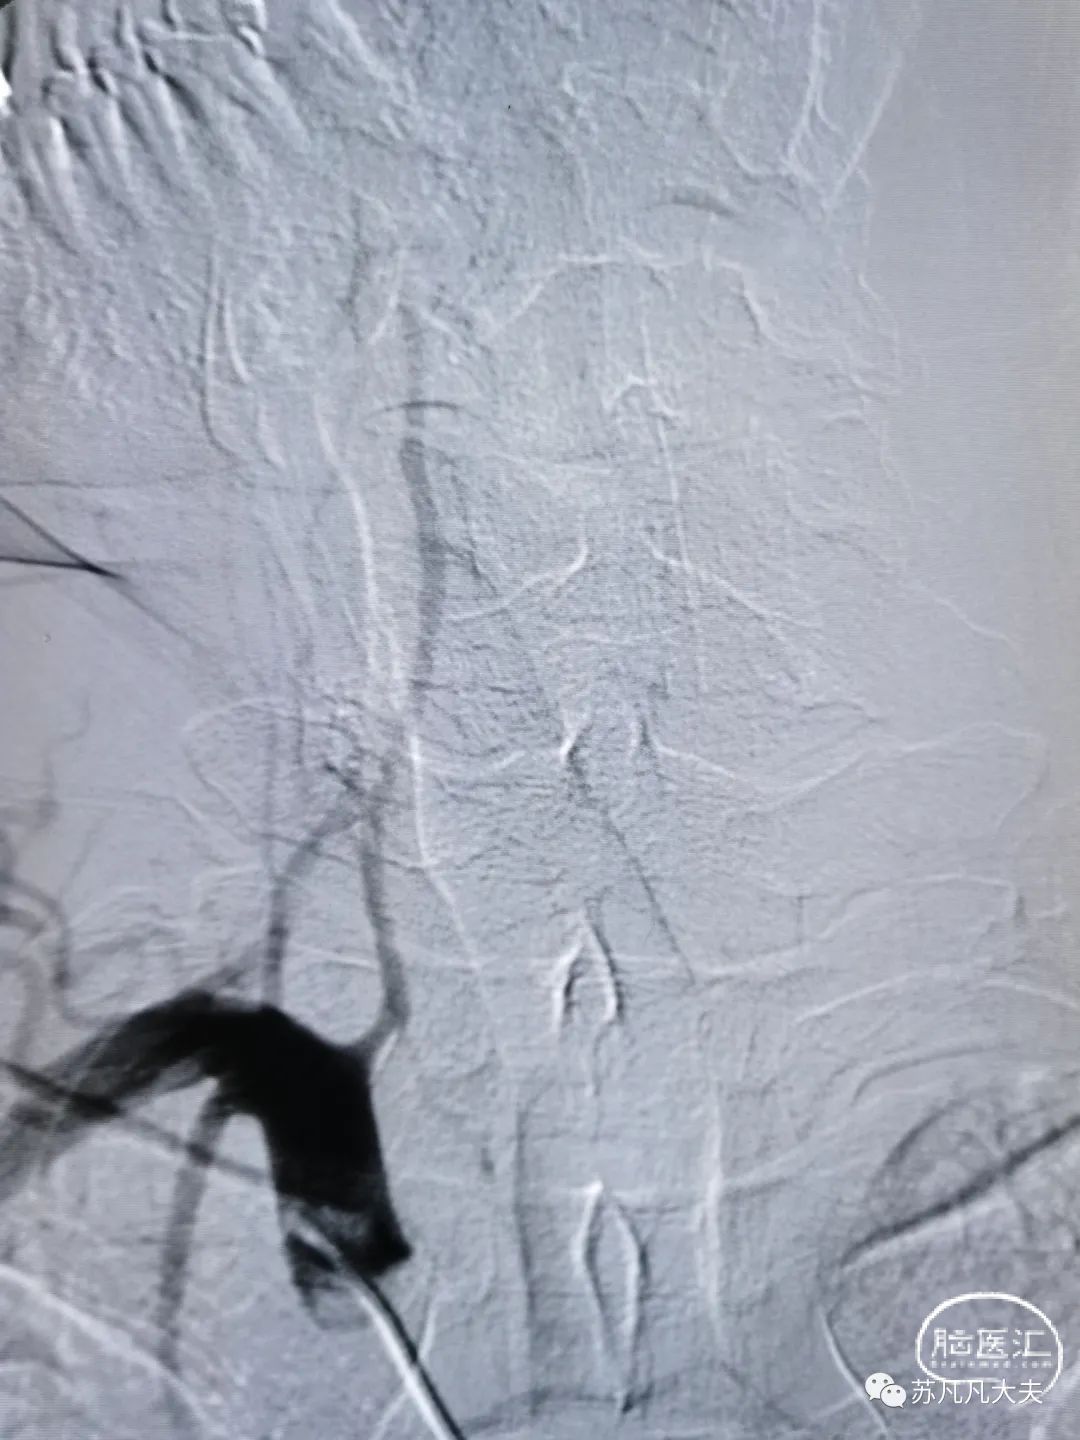

2.5/15球囊预扩后仍残余重度狭窄

4.5/13颅内支架定位,6atm释放

支架后颅内段狭窄解除

微导丝携微导管到达左侧大脑后动脉远端

微导管造影确认真腔

4/20取栓支架到位释放后造影

取栓后左侧大脑后动脉P1段再通

考虑患者大脑后动脉远端迂曲,继续取栓存在血管破裂出血风险,和家属交代后结束手术。

术后造影狭窄解除,颅内血供改善